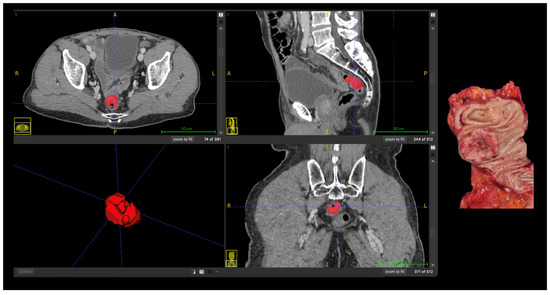

Machine Learning Radiomics in Computed Tomography for Prediction of Tumor and Nodal Stages in Colorectal Cancer

by Lara de Souza Moreno, Tony Alexandre Medeiros da Silva, Mayra Veloso Ayrimoraes Soares, João Luiz Azevedo de Carvalho and Fabio Pittella-Silva

Background/Objectives: Accurate preoperative TN staging is essential for guiding surgical and adjuvant treatment decisions in colorectal cancer (CRC), yet conventional imaging still faces limitations in reliably distinguishing early from advanced disease. This study aimed to evaluate whether CT-based radiomics combined with machine learning can noninvasively predict both tumor (T) and nodal (N) stages of CRC, and to identify which feature groups most contribute to each task. Methods: Fifty-three patients (55 tumors) with histologically confirmed CRC who underwent preoperative contrast-enhanced CT were retrospectively analyzed. A total of 107 radiomic features were extracted using PyRadiomics version 3.1.0, including shape, first-order, and texture features. Multiple preprocessing strategies—z-score normalization, PCA, and SMOTE—were tested across 11 machine learning classifiers. Results: For T staging, logistic regression using shape-based features achieved a mean sensitivity of 0.721, a specificity of 0.68, a balanced accuracy of 0.70, and an AUC of 0.751. For N staging, the AdaBoost model using texture-based features achieved a sensitivity of 0.742, a specificity of 0.622, a balanced accuracy of 0.682, and an AUC of 0.750. Shape features predominantly contributed to T prediction, while texture matrices drove N prediction, reflecting morphological and microstructural correlates of invasiveness and lymphatic dissemination. Conclusions: CT-based radiomics can quantitatively capture both morphological and textural patterns of tumor behavior, providing a noninvasive framework for preoperative TN staging in CRC. Full article